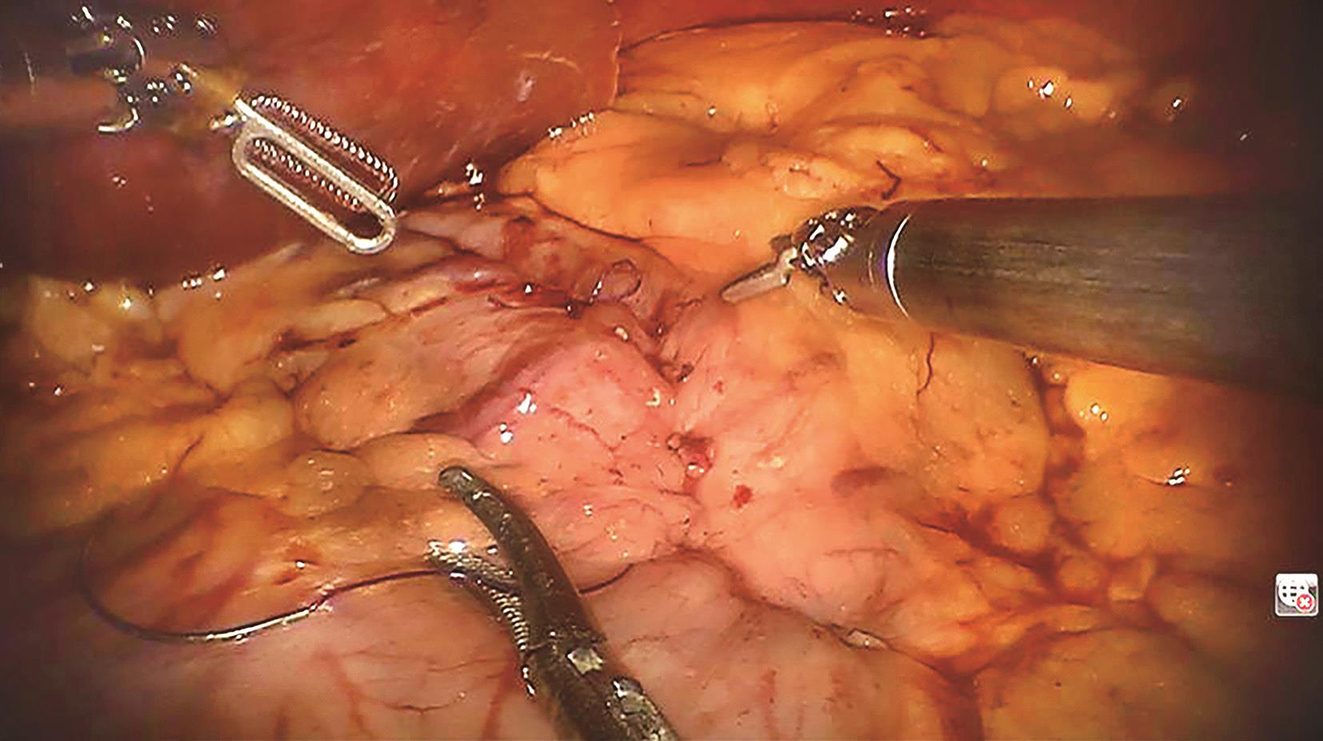

患者于加速康复外科(enhanced recovery after surgery,ERAS)理念指导下行术前准备,2016年9月27日行“机器人辅助下腹腔探查术+胃肿瘤切除术”。术中先行胃镜探查发现肿瘤位于胃底后壁近贲门处,大小约2.0cm×1.0cm;离断大弯侧网膜,暴露胃后壁瘤体,切开后壁肿瘤所对应胃前壁,以腹腔镜下切割吻合器于距离瘤体1cm处离断胃壁,完整切除肿瘤,将肿瘤置入标本袋中并用丝线结扎袋口,经绕脐半周切口取出,检查标本切缘安全,以可吸收线加固切口,缝合腹部戳孔及绕脐切口。手术过程顺利,手术时间60min,术中出血量约为10ml(图2~图5)。

图2 切开胃前壁

图3 丝线提起肿瘤

图4 切割吻合器切除肿瘤

图5 3-0可吸收线缝合胃壁